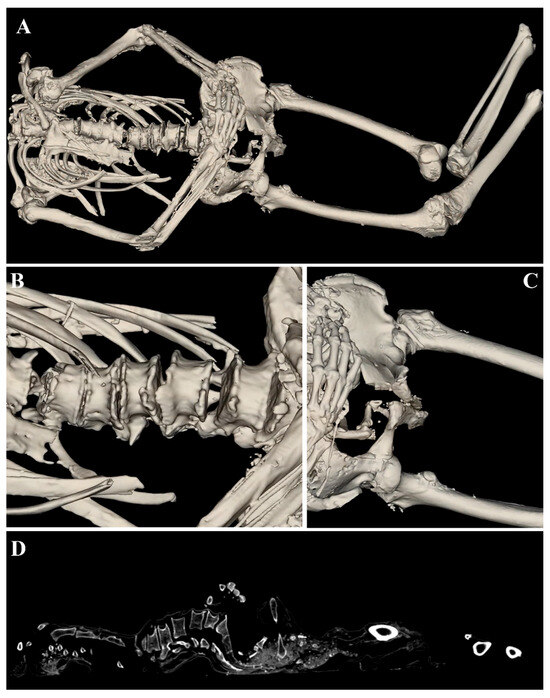

2. Materials and Methods

2.1. Samples

2.2. Anatomage Table

3. Results